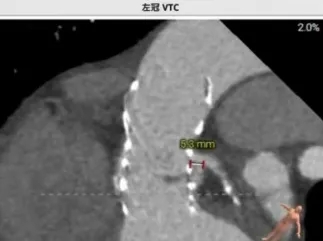

术前讨论:患者77岁老年男性,3年前行TAVR术,此次再发主动脉瓣关闭不全,经评估排除感染,考虑主动脉瓣生物瓣毁损,患者心衰重,消瘦、虚弱,经多学科讨论,TAVR in TAVR手术指征明确,考虑行TAVR in TAVR治疗,术前评估瓣架内径:瓣环26.6,LVOT 26.6,瓣架位于瓣环以下:5(无窦)-13(左窦)mm,左侧冠脉高度12.1,右侧13.4,左冠VTC5.3mm VT-STJ:0mm,右冠VTC4.4mm VT-STJ0mm, 主动脉弓部角度可,存在钙化,双侧髂股动脉内径可,右侧股动脉分叉位于股骨头平面中部 左侧股动脉分叉位于股骨头下缘中部,建议左侧入路,拟植入29号瓣膜,因患者冠脉风险大,需控制瓣膜植入深度,拟控制S3上缘位于启明第3-4个交接点处,同时需关注冠脉(Guidzilla预置保护)。

(1)TAVR in TAVR中需重点评估冠脉风险,相较于自体瓣膜评估,瓣中瓣植入过程中,需重点关注几个指标(图6):coronary risk plane(CRP),New-skirt Plane(NSP),VTA:VTC,VTAoS,VTSTJ。主要原因在于人工瓣膜将会形成新的封堵平面,术前评估中需重点关注。